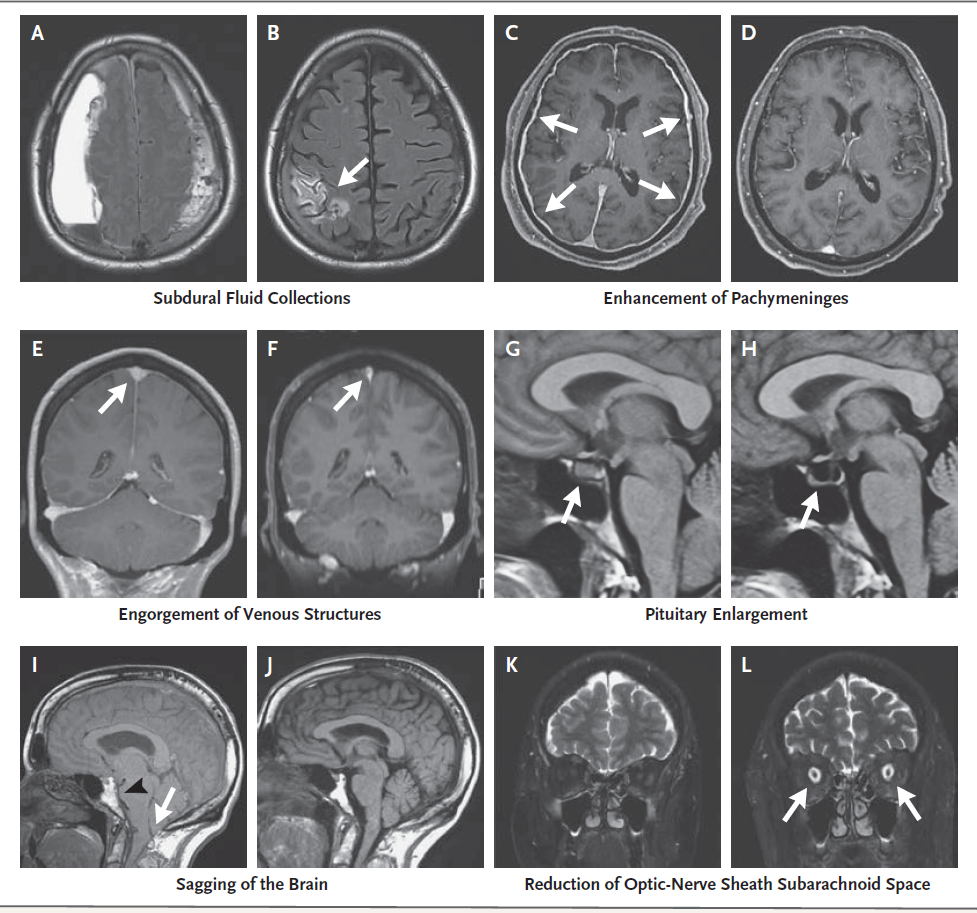

自发性颅内低压的诊断标准包括MRI增强的典型表现、脊柱成像的脑脊液漏或腰椎穿刺测量的脑脊液低压。增强MRI显示硬脑膜增厚,以及硬膜下积液、静脉结构充血、垂体增大、大脑下垂或视神经鞘蛛网膜下腔体积减小的特征厚脑膜强化其原因可能与颅内空间内脑脊液体积降低导致的颅硬脑膜静脉系统继发性扩张有关(Monro–Kellie学说)。但20%的自发性颅内低血压患者头部MRI表现正常